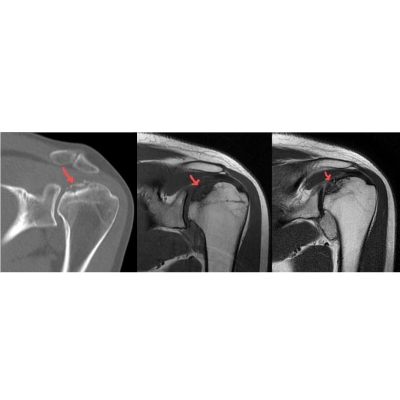

4. Paciente chega no seu consultório com dores agudas no cotovelo após queda com a mão estendida. Tirou uma radiografia, cujo laudo foi negativo. Em relação a esta imagem, qual das alternativas abaixo está INCORRETA?

6. Em relação aos cortes acima, da esquerda para direita, qual alternativa está correta?